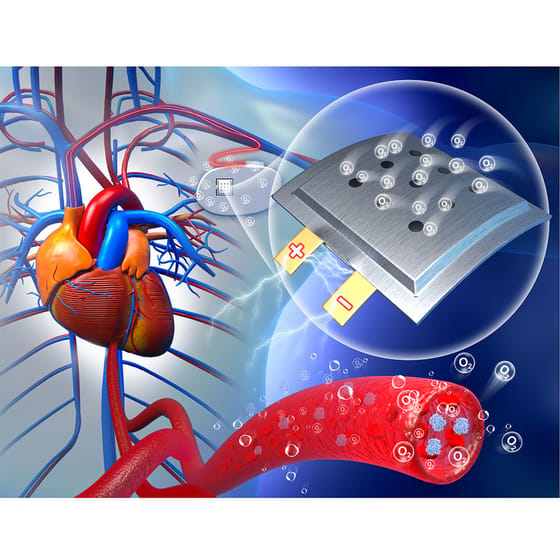

Reménysugár rengeteg betegnek: maga a szervezet lehet a beültetett eszközök akkumulátora

Kínai kutatók állatkísérlete reményt nyújt arra, hogy a jövőben a mostaninál jóval hosszabb ideig ne kelljen cserélni a szervezetbe ültetett orvosi eszközök akkumulátorait. A működtetéshez szükséges energiát ugyanis maga a szervezet adja.